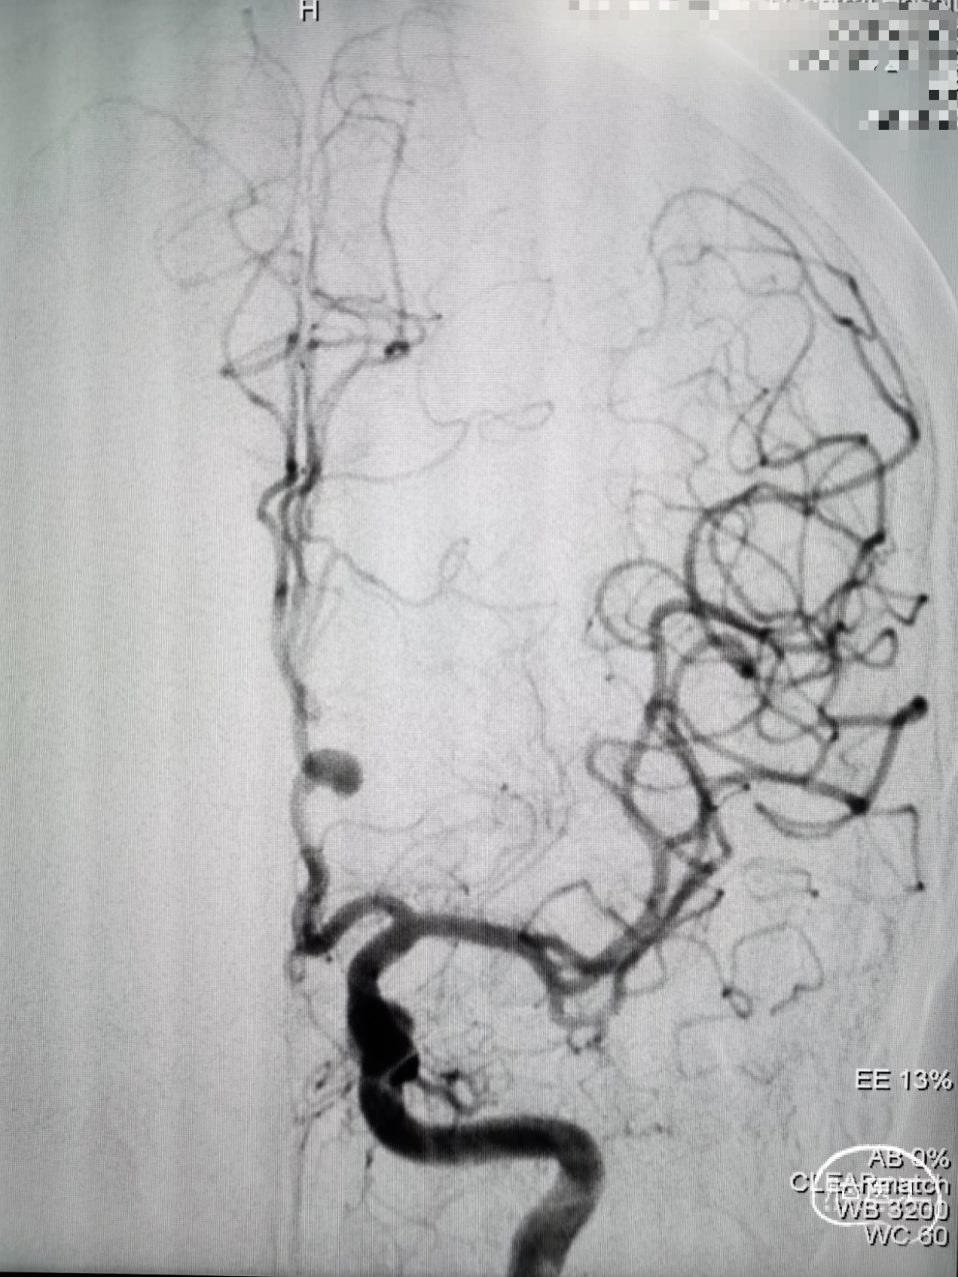

术后造影:支架内未见血栓形成

即刻造影

20分钟后造影

术毕正、侧位造影,血管及分支通畅,瘤腔内造影剂滞留,侧位可见明显“半月征”。

Dyna CT显示支架打开充分,贴壁良好。